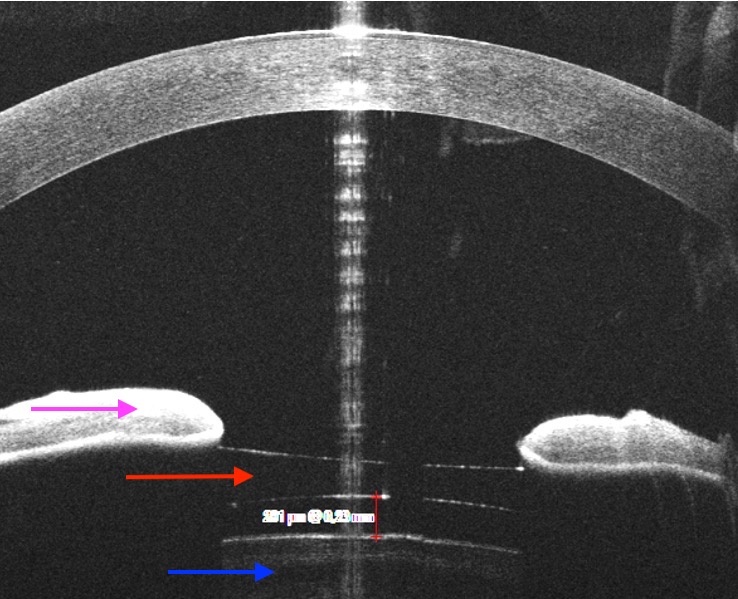

OCT de segment antérieur d'un implant phaque ICL (flèche rouge) entouré d'un liseré blanc en haut et d'un liseré blanc en bas qui sont les limites de l'implant.

Cet implant est localisé derrière l'iris (flèche rose) et devant le cristallin (flèche bleue)